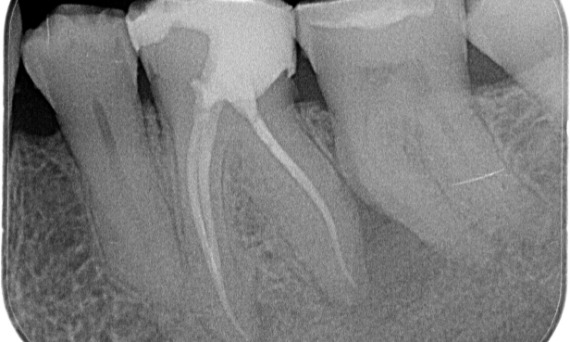

Un enfoque restaurador de la endodoncia

"Elegí TruNatomy para poder conservar la mayor cantidad de dentina posible y superar la carga oclusal y aumentar la longevidad del diente". - Dr. Abuelezz

Antes: Tras el examen, hubo una lesión de caries relacionada con el primer molar inferior derecho. El examen radiográfico reveló la proximidad de la lesión a la bocina pulpar y, al combinarla con la queja principal, se concluyó un diagnóstico final de pulpitis irreversible crónica.

Después: La cavidad de acceso se realizó de la manera más conservadora posible. TruNatomy fue el sistema de elección debido a la edad del paciente joven. Necesitábamos preservar la dentina tanto como fuera posible para aumentar la capacidad del diente y así superar la carga oclusal y aumentar la longevidad de la restauración final.